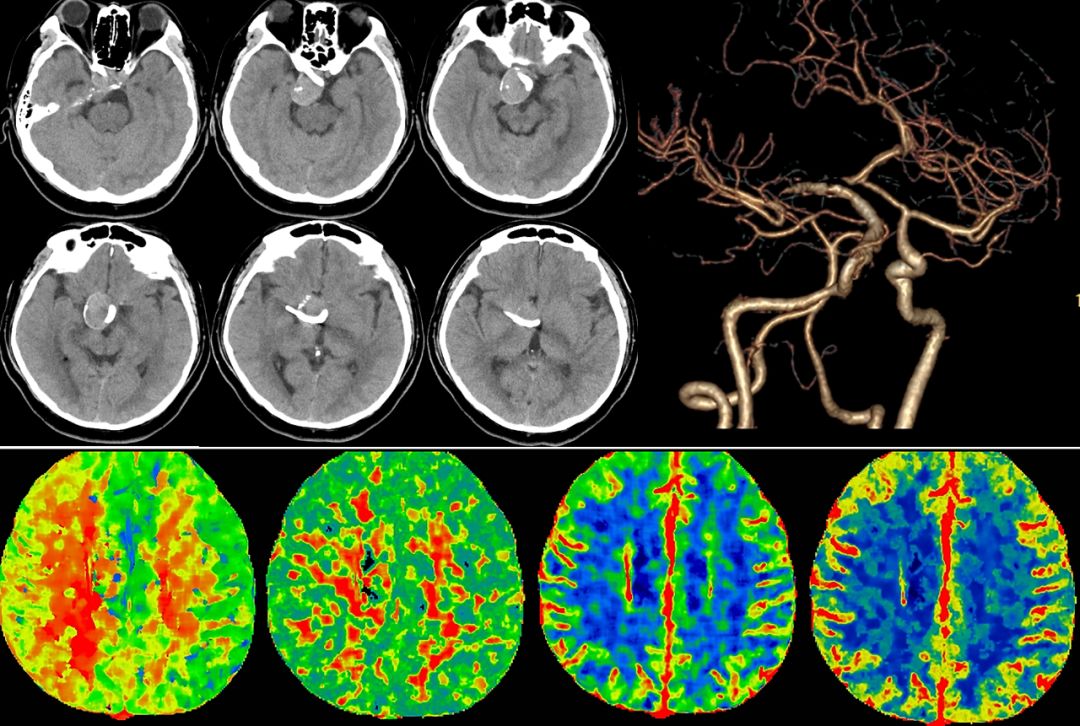

辅助检查:磁共振血管成像(MRA): 右侧颈内动脉夹层动脉瘤。

术前造影:

(1)右侧颈内动脉海绵窦段至颈内动脉末端巨大夹层动脉瘤伴血栓形成(图1)。

图1

(2)左颈动脉造影见大脑前动脉抬高,右侧颈内动脉球囊闭塞试验见前交通动脉开放,M1段显影不良,考虑后交通供血较强(图2)。

图2

(3)后循环造影及右侧颈内动脉球囊闭塞试验,提示后交通供血较明显,可见动脉瘤显影,无法闭塞颈动脉,选择行动脉瘤栓塞术(图3)。

术后复查影像(图11)。

图11